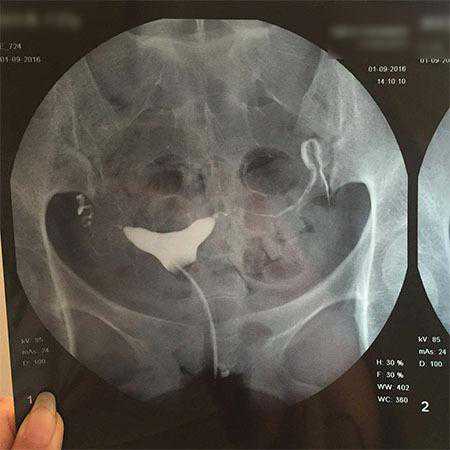

从你提供的片子来看:子宫显影,形态正常,未见充盈缺损与龛影。双侧输卵管部分显影,右侧城串珠样改变,左侧走形欠自然。双侧输卵管均仅见少量造影剂溢出,盆腔弥散欠佳。初步印象,双侧输卵管不全梗阻(通而不畅)。患者已在医院诊断多囊卵巢综合症。促排卵治疗三次,均有卵泡发育,有排卵,未怀孕。通过审阅造影片子,输卵管通而不畅是造成这位患者不孕的主要原因。